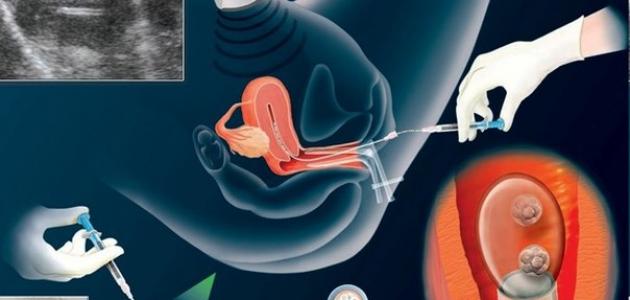

تعتمد عملية الحقن المجهري على مجموعة من الخطوات من أهمها:

يجب أن تتناول المرأة أدوية الخصوبة التي تزيد من نشاط المبايض وذلك لتنشيط البويضات الجاهزة للإخصاب، ثم يجري الطبيب خلال هذه الفترة فحوصات دم وتصوير بالموجات فوق الصوتية، لتحديد الوقت الذي تصبح فيه البويضة جاهزة للإخصاب.

يحتاج الطبيب عينة من من الحيوانات المنوية الخاصة بالزوج في نفس اليوم الذي تكون فيه البويضة جاهزة للإخصاب، وقد يتسائل البعض هل عملية اطفال الانابيب تحتاج تخدير خاصة إذا كانت هذه العينة لا تحتوي على حيوانات منوية قد يلجأ الطبيب إلى الجراحة لاستخراجها، إذ يستخرج الحيوانات المنوية من الخصية باستخدام إبرة دقيقة، ويعتبرهذا الإجراء بسيطا ويكون تحت التخدير الموضعي.

وفي بعض الأحيان يتم تجميد بعض الحيوانات المنوية في حال الحاجة لتكرار هذا الإجراء فيما بعد، بعد أن تصبح البويضة جاهزة للإخصاب، تستخرج البويضة باستخدام إبرة دقيقة مجوفة وتسير مسارها من خلال الموجات فوق الصوتية، وقد يندهش البعض ويتسائلون هل طفل الانابيب يشبه الاب ام الام خاصة مع تتناول المرأة هرمون البروجسترون على شكل حبوب أو حقن أو هلام بهدف تجهيز بطانة الرحم لاستقبال الجنين.

ثم يعزل حيوان منوي واحد في المختبر ويحقن في البويضة الجاهزة للإخصاب، وبعد يوم واحد تصبح البويضة المخصبة جنينا، بعد ذلك ينقل الطبيب جنينين أو اثنين إلى الرحم من خلال عنق الرحم باستخدام أنبوب دقيقة وبمساعدة الموجات فوق الصوتية.

عملية اطفال الانابيب بالتفصيل:

إجراء تحليل للدم، تصوير الرحم وقناة فالوب وتحليل الحيوانات المنوية.

مرحلة تنشيط المبايض لعمل أطفال الأنابيب.

يعطي الطبيب المختص في هذه المرحلة بعض الأدوية والعقاقير الطبية المحفزة لإنتاج بويضات سليمة وصالحة لاستخدامها في عمل زرع أطفال الأنابيب، وهذه الخطوات تسعد بصورة كبيرة في الحصول على أكبر عدد ممكن من البويضات في الدورة الواحدة.

مرحلة مراقبة البويضات باستخدام جهاز الألتراساوند.

تبدأ مرحلة مراقبة البويضات لتحديد حجم البويضات النافعة وعددها، وتقليل فرص حدوث أي مضاعفات للمريضة من خلال المراقبة المستمرة، ثم تأتي مرحلة سحب البويضات من المبيض.

تعليمات قبل عملية سحب البويضات:

يكون سحب البويضات من المبايض عن طريق إجراء عملية جراحية صغيرة بعد تخدير جسم المريضة، حيث يتم سحب البويضة من السائل الموجود فيها، مع مراعاة حجم البويضات قبل السحب ليتم بعد ذلك فحصها بالمختبر للحصول على البويضات الناضجة فقط لاستخدامها في عملية طفل الأنابيب، يلجأ الأطباء في حالة أنها غير كافية، إلى تأجيل العملية إلى حين موعد الدورة الشهرية التالية.

مرحلة تحضير الحيوانات المنوية:

يتم الحصول على عينة من السائل المنوي بالشكل الطبيعي، أو المسمى بالقذف من الرجل وذلك من أجل إتمام عملية زرع أطفال الأنابيب، وهنا نلاحظ أن البويضة الواحدة تحتاج إلى عدد يتراوح بين عشرة آلاف إلى مائة ألف حيوان منوي، ليتمكن واحد منها من اختراقها.

مرحلة الحقن وتخصيب البويضات:

يجمع الطبيب الحيوانات المنوية مع البويضة في وعاء مخبري يشبه الحياة الطبيعية داخل الرحم، ويبقى مرحلة الانتظارليتمكن حيوان منوي واحد فقط من اختراق البويضة حتى تتم عملية الإخصاب بعد وضعها في الحضانة.

بعد تخصيب البويضة، يبدأ الطبيب في تقسيمها والكشف عن وجود أي أمراض وراثية لدى الزوجين من خلال تقنية خاصة لفحص المادة الجينية للأجنة قبل مرحلة عملية ترجيع الأجنة داخل الرحم.

نقل الأجنة إلى الرحم:

تعتبر هذه المرحلة من أصعب مراحل أطفال الأنابيب، كم يوم تستغرق عملية اطفال الانابيب وعادة ما تتم بعد خمسة أيام من التلقيح الصناعي وتخصيب البويضة، حيث تنقل الأجنة إلى رحم الأم من خلال أنبوب مخبري رفيع يمر بعنق الرحم حتى يصل إلى التجويف الرحمي الداخلي.